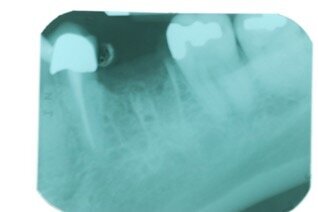

Le radiografie eseguite immediatamente dopo l’intervento chirurgico con la tecnica GBR hanno indicato che l’alveolo post-estrattivo era stato adeguatamente zeppato con granuli di osso bovino decellularizzato (Fig. 7). Il richiamo a 6 mesi, ha mostrato tessuti molli in buona salute senza la presenza di segni di infiammazione (Fig. 8). La radiografia periapicale ha mostrato la perfetta guarigione dell’alveolo post-estrattivo (Figg. 9, 10). Anche durante l’esposizione ossea per il posizionamento dell’impianto, l’osso appare in buona salute e non sono presenti granuli di biomateriale non integrato. La membrana di pericardio bovino è completamente riassorbita (Fig. 11).

La radiografia eseguita immediatamente dopo il posizionamento dell’impianto ha mostrato che gli impianti dentali erano perfettamente posizionati a livello dell’osso crestale (Fig. 6). Le analisi istologiche della carotatura di osso prelevato hanno mostrato che a 6 mesi dall’intervento di conservazione dell’alveolo, si è formato nuovo tessuto osseo vitale e sono ancora presenti granuli del biomateriale utilizzato (Fig. 12). Il follow up radiografico a 3 anni indica una situazione ossea invariata con l’impianto ancora a livello dell’osso crestale. La parte protesica ancora in buone condizioni senza segni d’infiammazione, né si sono riscontrate mucositi o perimplantiti. I restauri privi di complicanze tecniche.